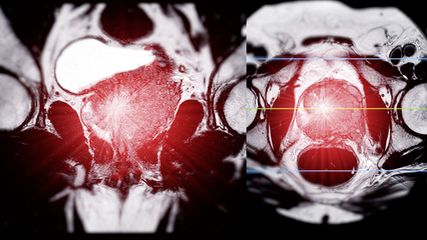

Therapiestrategien beim hormonsensitiven Prostatakarzinom